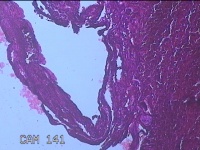

性别

女

年龄

45岁

临床诊断

四肢皮脂腺囊肿

一般病史

发现右侧大腿结节半年余。

标本名称

右侧大腿结节

大体所见

灰白暗红色组织1.5x1x0.8cm一块,表面带梭形皮肤1.3x0.7cm,皮下见结节1.3x1x0.7cm一个,切开结节呈实性,切面灰白 暗红色,质软。

图3